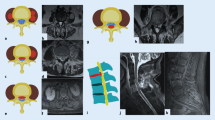

In MRI, during the progression of bacterial spondylodiscitis, the disc often becomes a focal point for fluid collection. In axSpA, however, the disc usually retains its regular signal intensity or shows only signs of degeneration. Therefore, in axSpA, variations in signal intensity are likely to be limited within the vertebral body and the vertebral end plate, but not in the disc. Furthermore, perivertebral effusion and intradiscal effusions are rarely seen in discovertebral lesions in axSpA. The high signal intensity on T2-weighted images observed in Andersson's lesions usually corresponds to granulation tissue, and high-intensity T2 peripheral areas reflect infiltration of tissue and inflammatory cells, not fluid collection (Fig. 3). The lack of intradiscal or perivertebral fluid collection is an important diagnostic sign [13].

Sagittal T1-weighted image (a), sagittal T2-weighted image (b) and sagittal STIR image (c) showing a typical active Andersson lesion at D7/D8, with subchondral edema-osteitis, discitis and erosions (arrow). Romanus lesions can be observed in the anterior corners of the vertebral bodies at D6, D7 and at L1 and L2 (arrowheads)